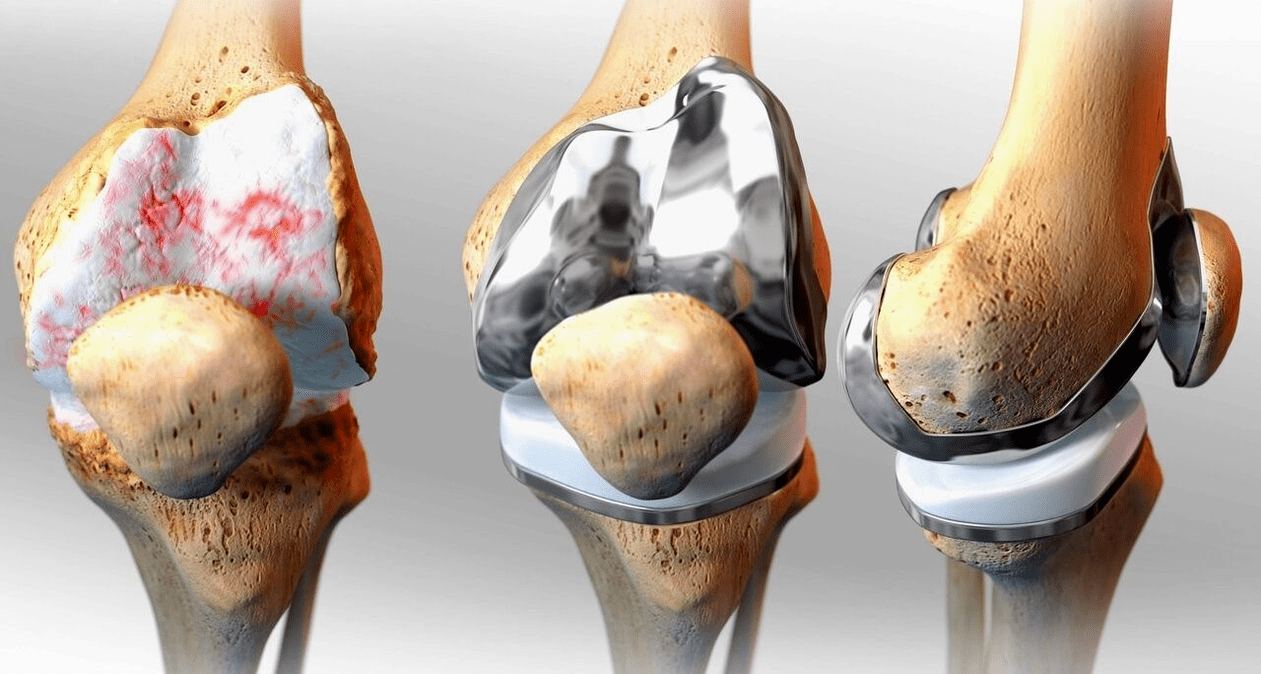

Surgical treatment and endoprosthesis

Endoprosthesis replacement is a common and effective surgical method in the treatment of severe gonarthrosis, which allows you to maintain the mobility of the limbs and the ability to lead a full life later.This is a high-tech operation that lasts approximately an hour and a half.Postoperatively, long-term rehabilitation and development of the joint are necessary.After 25-30 years, when the artificial joint wears out, it needs to be replaced again.